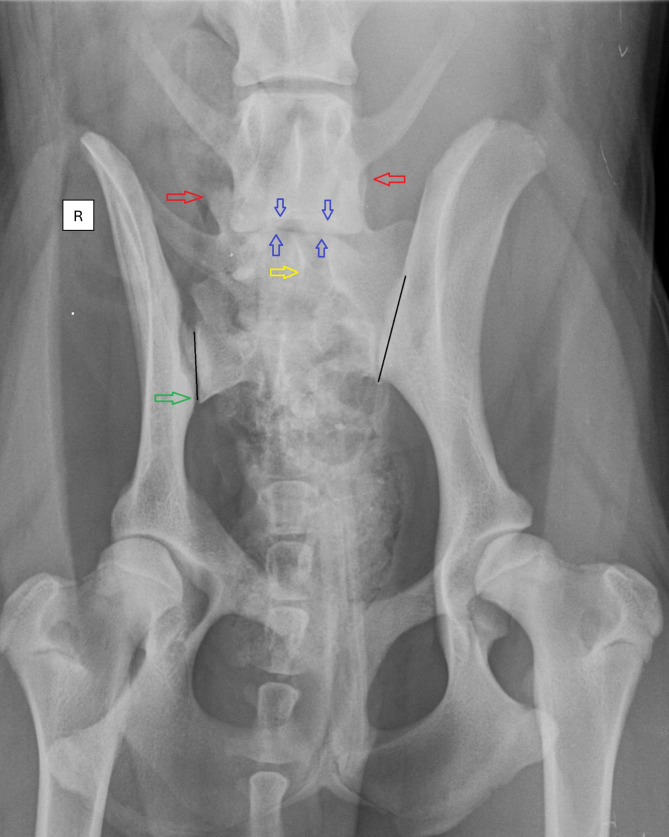

Background: A lumbosacral transitional vertebra (LTV) is a congenital anomaly of the caudal vertebral column. It has been associated with asymmetrical canine hip dysplasia (CHD) and cauda equina syndrome (CES) in German Shepherd dogs. This retrospective cross-sectional study aims to report the potential influence of asymmetric LTV on pelvic anatomy using ventrodorsal (VD) radiographs.

Results: The results are based on the evaluation of VD radiographs of 13,950 dogs from 14 breeds; an LTV was identified in 18.5%. The LTV segments were allotted into symmetrical (78.6%) and asymmetrical (21.4%) categories. An asymmetrical CHD grade was observed in 12.4% of the dogs, of which 39.7% had asymmetrical LTV. An asymmetric LTV was associated with an uneven sacroiliac joint length, in which the shortest sacroiliac joint is positioned more caudally, resulting in a reduced distance to the hip joint (P < 0.001). Rotation of the asymmetrical LTV segment about the long axis was associated with opposite pelvis rotation vertically (P < 0.001). Also, long-axis rotation of the asymmetric LTV segment was associated with an elevation of the pelvis (P < 0.001), promoting an asymmetrical CHD grade (P < 0.001).

Conclusions: This study suggests a compensatory mechanism for the sacroiliac joint related to an asymmetrical LTV. Counter-rotation between the pelvis and the LTV segment vertically may straighten the lower back. The asymmetrical LTV segment most likely affects the rotation of the pelvis and may indirectly promote an asymmetrical CHD grade.